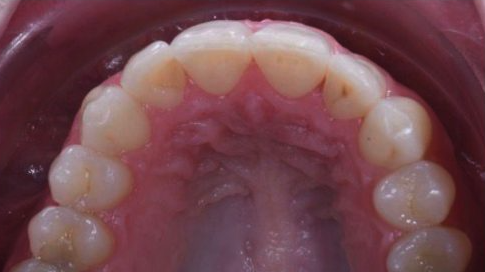

Severe Crowding

Upper front teeth realigned using invisalign series of aligners without removing any teeth.